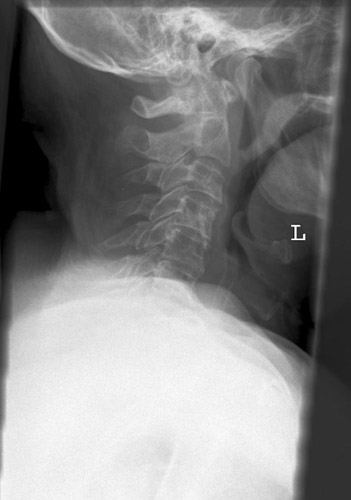

HWS seitlich

Fehler

Der unterste Halswirbel wird durch die Schultermuskulatur verdeckt.

Abhilfe

Arme des Patienten stark nach unten ziehen, am besten mit Gewichten beschweren (evtl. Spezialaufnahme in der Stellung des "Wasserskifahrers" "Übergang") .